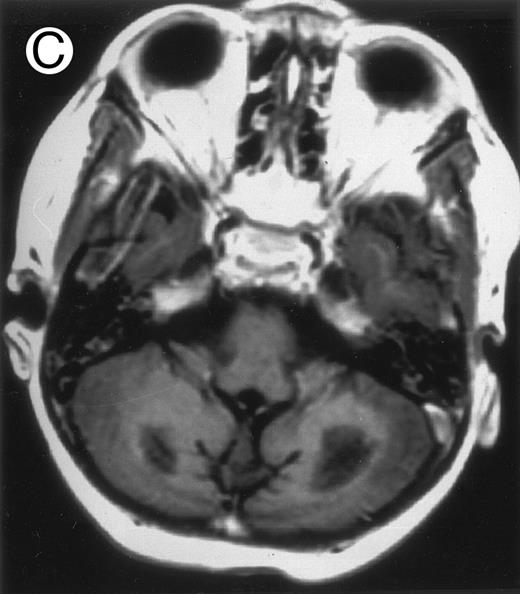

Three different aspects of brain imaging in HLH patients. (A) CT scan of a 3-month-old baby showing a large subdural effusion, several necrotic areas and hypodensities of the white matter. (B) Brain magnetic resonance of a 14-month-old boy showing large confluent areas of hypersignal in T2-weighted images. (C) Large symmetrical necrotic areas of cerebellar white matter in a 41/2-year-old girl (MRI).

Together, 19 patients had primary severe CNS disease progression or CNS relapse (Fig 1). Three of 19 had a CNS relapse characterized by meningitis only. Neurological symptoms occurred in 16 of these 19 patients (9 from the onset and 7 after the initial meningitis) (Fig 1). No clinical or neuroradiological difference was detected between the patients who developed neurological symptoms as the initial CNS manifestation or after initial meningitis (Table 1). The occurrence of these neurological manifestations marked a turning point in the evolution of the disease, as chemotherapy led to an improvement of the neurological symptoms in only three patients despite the use of intensive treatment by MTX IT. In these three patients, neurological sequelae persisted after the first symptoms and a relapse occurred within 3 to 10 months. Brain imaging was repeated during chemotherapy for four patients with progression of the CNS disease: in three patients, a severe brain atrophy developed (Fig 3A and B) and in the last patient who initially had contrast enhancement in cerebellar white matter, a cerebellum parenchymal loss was observed (Fig 2C). All of these 19 patients treated by chemotherapy only (n = 15) died during a last episode of coma and brain stem symptoms associated with a systemic hemophagocytic syndrome, 6 ± 6 months after the first neurological symptom (irrespective of the age at this first event). Four of these 19 patients were transplanted (one patient received an HLA-identical BMT, three an HLA-partially identical BMT). Median delay between diagnosis and BMT was 14 months (range, 2 to 20 months). All of these four patients died of BMT-related toxicity and/or disease progression.